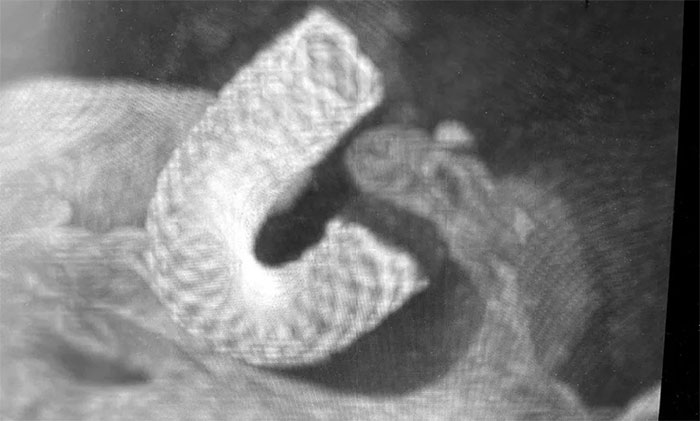

经充分完善术前准备,席刚明教授在麻醉科和介入手术室紧密配合下,开展右颈内动脉眼动脉段动脉瘤血流导向装置(Pipeline)置入术。手术历时两个小时,顺利“拆除”了埋在患者脑子里的“不定时炸弹”。

▲ 造影显示血流导向装置贴壁良好